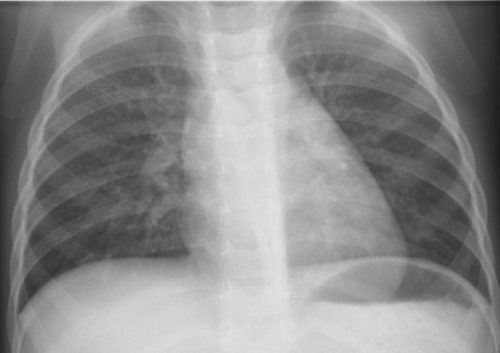

60代、微熱軽度の息苦しさ発病後7日目(COVID-19軽症)